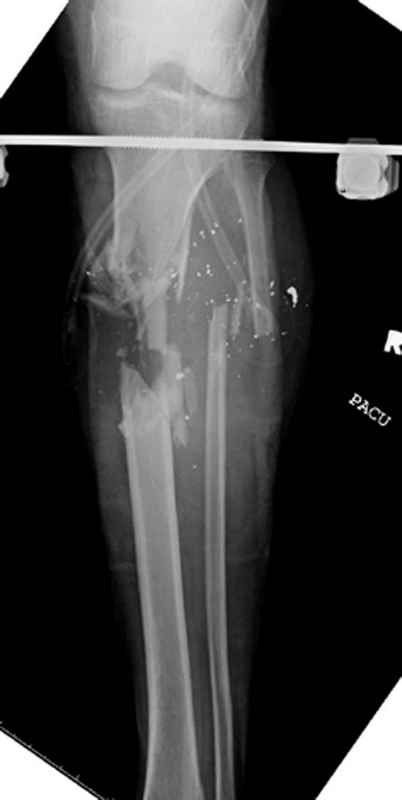

Здесь представлен больной 27 лет с ранениями, включая огнестрельный перелом большеберцовой кости.

11.08.09 доставлен в операционную, Irrigation&Debridment c фиксацией Наружным Фиксатором и вакуумирование VAC; службой травмы пройзведена ангиография с негативным результатом. (снимки 1-10)

Имя     : 1 gsw tibia ap injury.jpg

Тип     : image/jpeg

Размер  : 22649 байтов

Описание: отсутствует

Url     : http://weborto.net:8080/pipermail/ortho/attachments/20090831/f744a2dd/attachment-0014.jpg